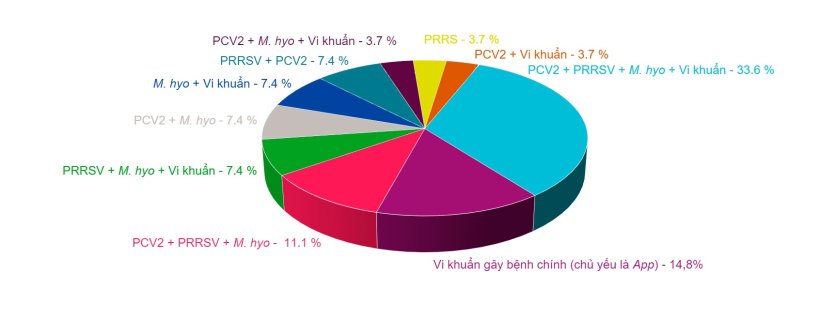

Hình 1: Sự kết hợp các bệnh lý được tìm thấy trong các ca nhiễm PRDC được chẩn đoán trong bốn năm qua bởi Dịch vụ giải phẫu bệnh lý thuộc Khoa Khoa học Thú y của Đại học Murcia.